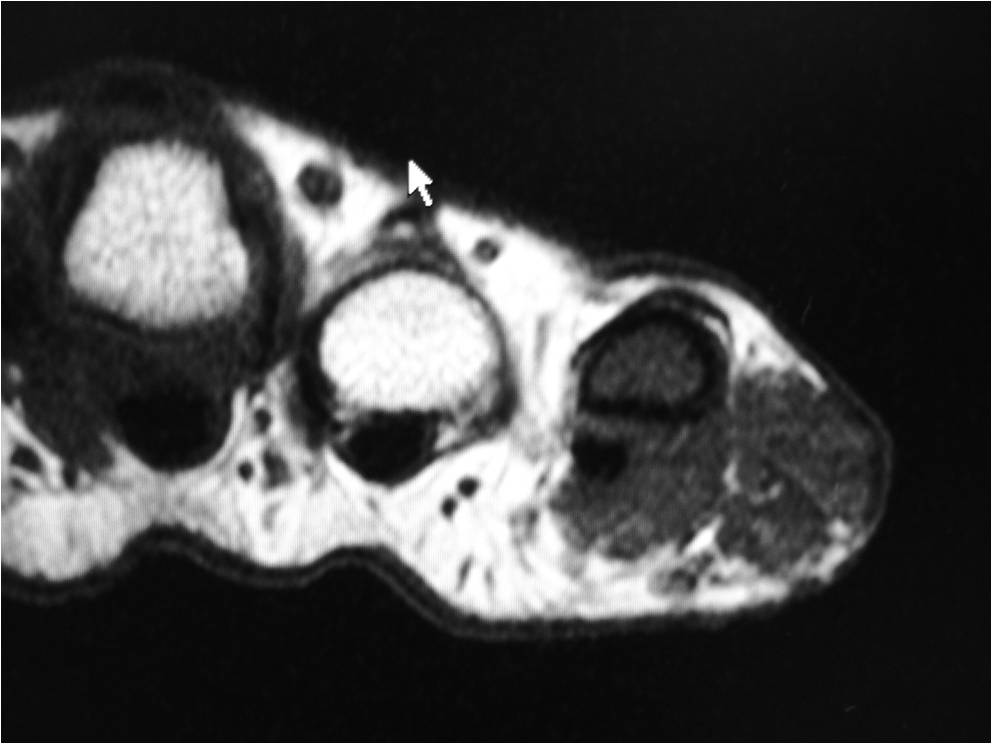

MRI

• Isointense to muscle T1

• Low to intermediate T2

• May bloom on gradient echo (hemosiderin deposition)

• May demonstrate intense enhancement

Fig. 2-5: MR images of the hand with a giant cell tumor of tendon sheath shows a mass isointense to muscle on T1W and intermediate to high signal on T2W images. The lesion does not infiltrate the bone.